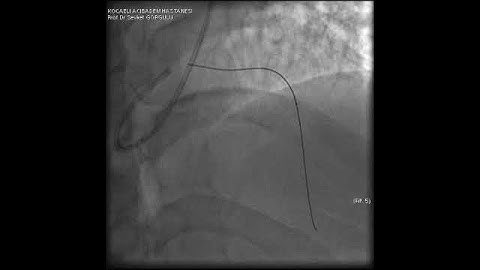

Microcatheter Tip Fracture During LAD CTO PCI: A Complication Video 3